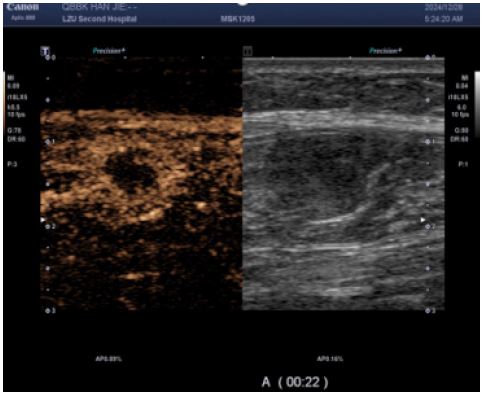

Figure 3: CEUS suggested heterogeneous hyper-enhancement at 12 s of contrast injection.

Images are Not Display Check it

Figure 4: The enhancement borders were clear, and areas of non-enhancement were seen within them; Irregular non-enhancing areas are present throughout the enhancement pattern, consistent with a benign enhancement pattern.

CEUS (performed next day): Subsequent CEUS performed 24 hours post-initial scan demonstrated heterogeneous enhancement at 25 seconds post-contrast injection, characterized by peripheral hyper-enhancement and a large central non-enhancing area – an imaging pattern misinterpreted as indicative of a benign lesion.

The reasons for the misdiagnosis of this patient as a benign tumor were as follows: (1) The initial diagnostic context involved routine ultrasound without documented extramuscular malignancy, precluding sufficient justification for metastatic suspicion; (2) Sonomorphological mimicry manifested as well-circumscribed, spindle-shaped anechoic foci with smooth margins, distinct hyperechoic capsules, and posterior acoustic enhancement within the calf musculature—features pathognomonic for schwannoma yet discordant with the infiltrative borders characteristic of aggressive malignancies; (3) Vascular analysis (Figure B) revealed sparse punctate vascular signals rather than the abundant internal/peripheral flow or large perforating vessels typical of subcutaneous cancers; (4) CEUS kinetics further reinforced misdiagnosis through arterial-phase peripheral hyper-enhancement with central non-enhancing zones, maintained circumscribed margins, and early washout in adjacent tissues—collectively aligning with classical benign enhancement profiles and creating a compelling illusion of non-malignant pathology.